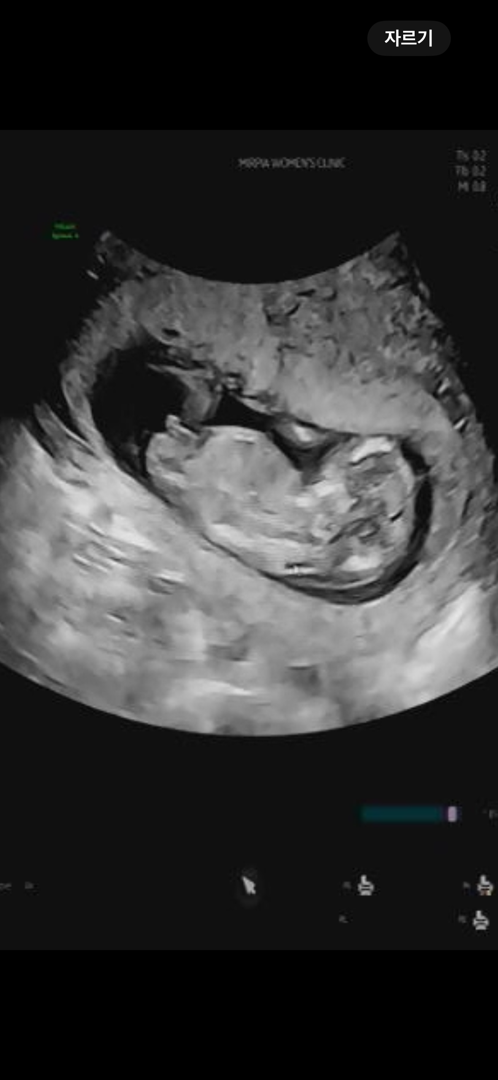

12주 3일차 각도법 봐주세요~!

다리 사이에 저게 정말이지 🌶️같은데,, 남자로 보이시나요 여자로 보이시나요🥹

끝에가 올라가 있어서 아들 같아요!